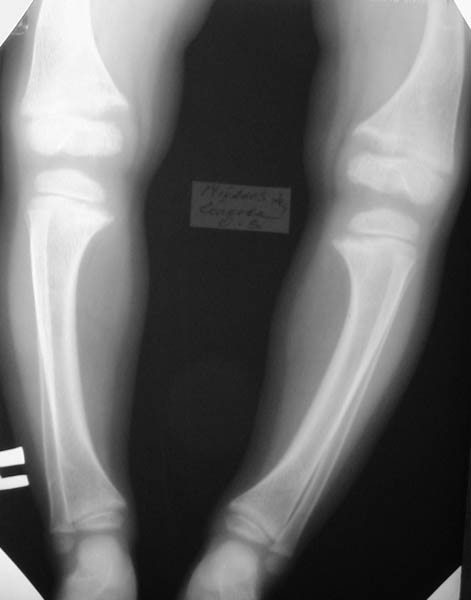

ТазКистиГолени

Девочка, 3 года 11 мес. Дз: Фосфатдиабет (витамин Д-резистентный рахит).

Жалобы на задержку роста. Общие анализы крови и мочи без особенностей.Биохимический анализ крови: билирубин 7,7, АЛТ 0,30, общий белок 73, креатин 0,061, щелочная фосфотаза 49%мл/г, K+ 4,4, Na+ 139, Ca++ 0,93, Ca общий 2,5.УЗИ органов брюшной полости: норма, печень увеличена, паренхима однородна, сосудистый рисунок сохранен. Рентгенологический возраст 2 года, хронологический возраст 4 года. Ранее рекомендована ЛФК, витамины, видеин.Рекомендации по лечению? Заранее благодарен! С уважением, А.В.Владзимирский Донецкий НИИ травматологии и ортопедии